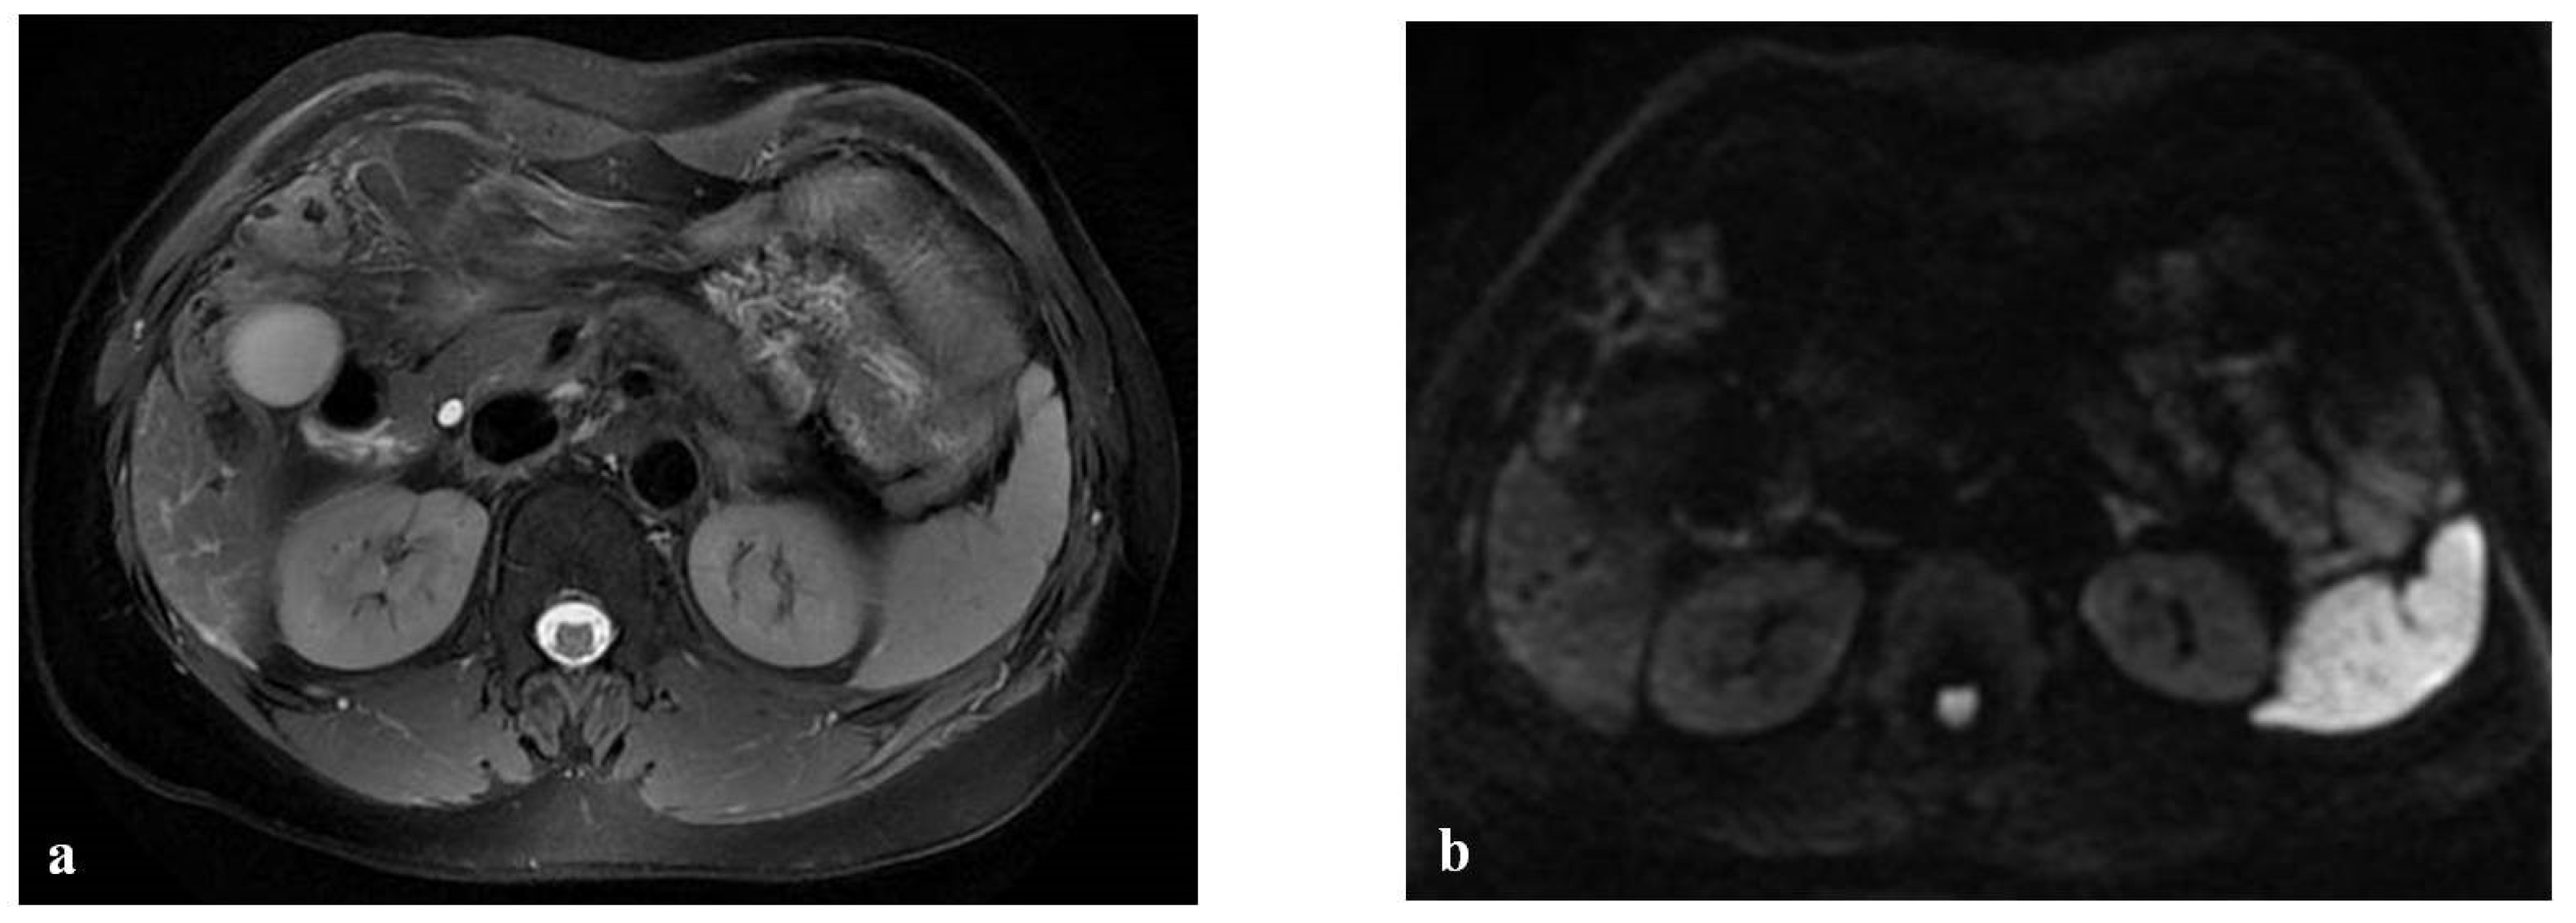

- Han, N.Y.; Park, B.J.; Sung, D.J.; Kim, M.J.; Cho, S.B.; Lee, C.H.; Jang, Y.J.; Kim, S.Y.; Kim, D.S.; Um, S.H.; et al. Chemotherapy-induced focal hepatopathy in patients with gastrointestinal malignancy: Gadoxetic acid–enhanced and diffusion-weighted MR imaging with clinical-pathologic correlation. Radiology 2014, 271, 416–425. [Google Scholar] [CrossRef]